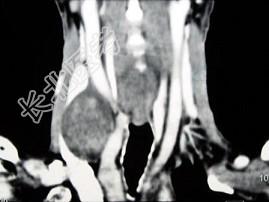

- 多项选择题男,70岁, 右侧颈部无痛性肿块3个月,CT扫描如图所示, 正确的描述或诊断是 ( )

A、右侧颈动脉间隙内见类圆形软组织肿块影,密度欠均匀,边缘光整

B、右侧颈静脉被推压至肿块外后方

C、右侧颈动脉被推压至肿块内后方

D、迷走神经源性肿瘤

E、交感神经源性肿瘤